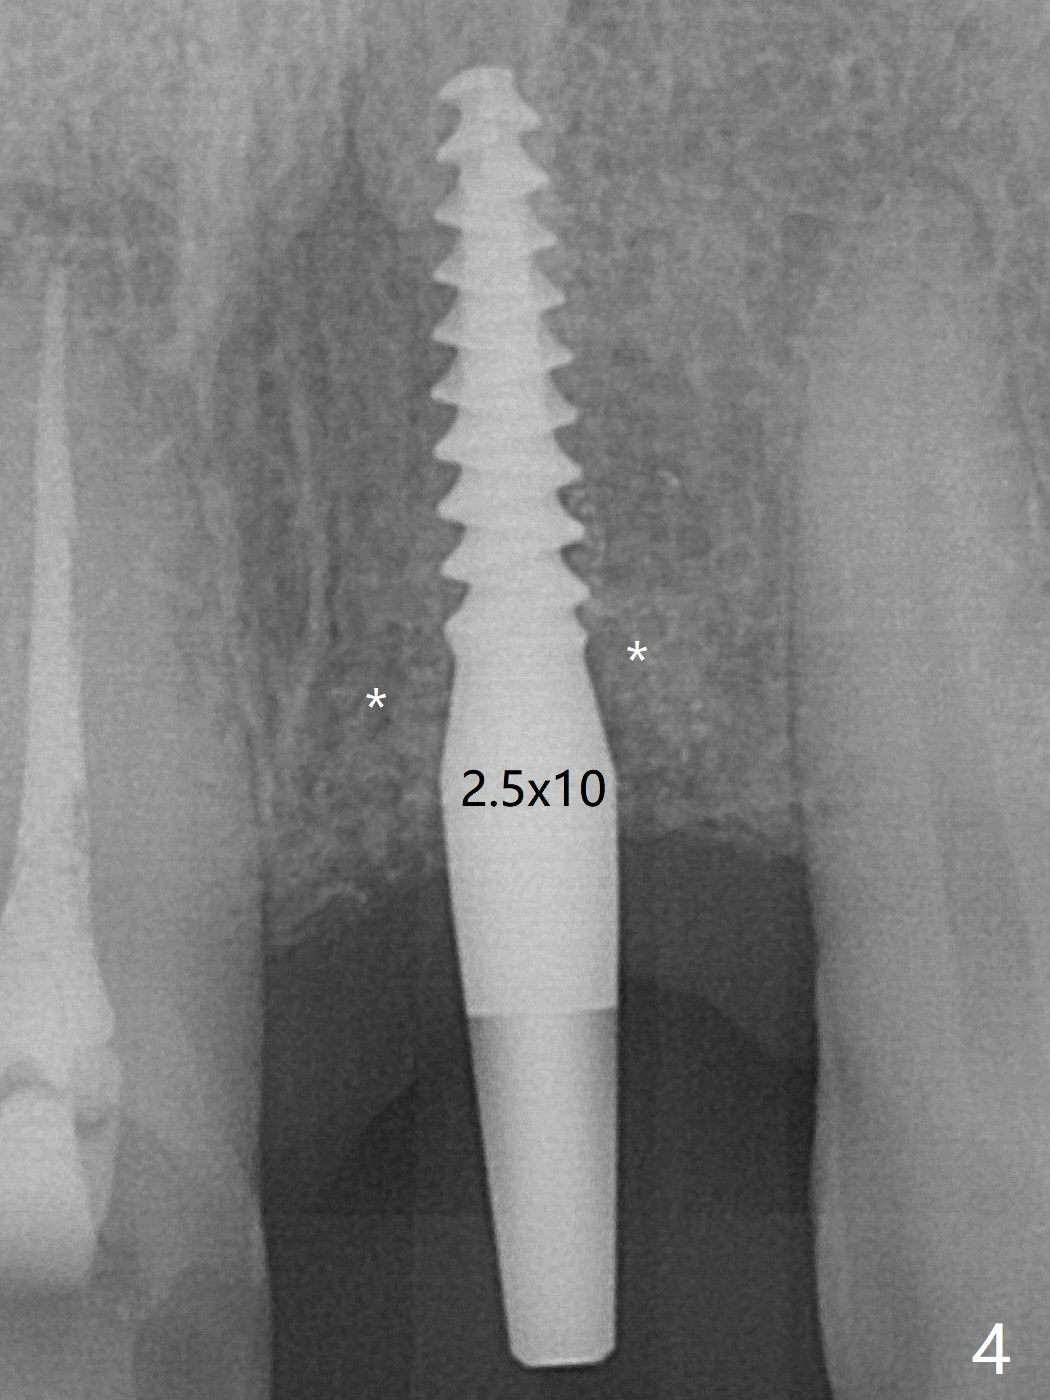

Except the depth, a 2.5x10 mm mini implant is placed with precision (in trajectory) at #9 (Fig.4 *(bone graft palatal)).